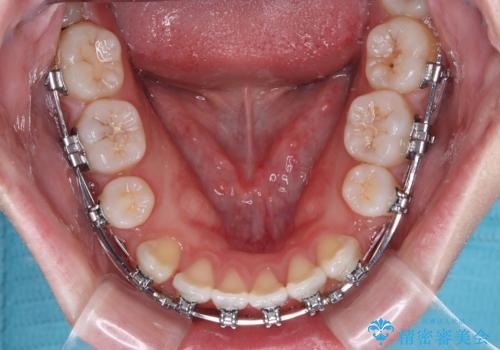

- メタルブラケット

上下左右の第一小臼歯4本を抜歯し、ワイヤー装置での抜歯矯正を行っていくのですが、原因である舌の突出癖を改善しないことには治療がうまく進められないため、舌のトレーニングを徹底するよう指導していくこととしました。

当初は舌のトレーニングをしっかりと行ってくださったおかげで、短い期間で治療を終えることができました。